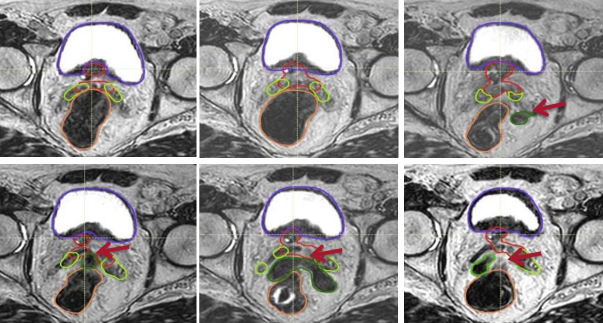

皇家马斯登医院的前沿放疗设备

放疗团队的物理师、影像师、放疗师这些团队成员的水平,共同决定了放疗的精准度以及患者的预后。

由于放疗会有很多次,因此随着次数增加,原本的肿瘤很可能会缩小,那么所需的放疗剂量也没有初始阶段那么大了。所以精准放疗,会需要随着治疗进程不断精准调整剂量,从而降低患者的损伤。

所以说,放疗看似简单,但实际上为了达到真正的“精准”,是一件极度耗费精力、时间的治疗方式。同样的设备,不同的精准度,对患者的预后可能会有很大差别!